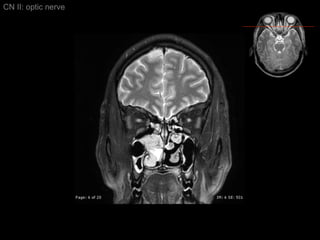

CN II: optic nerve Axial T2/ inferior to superior

CN II: optic nerve